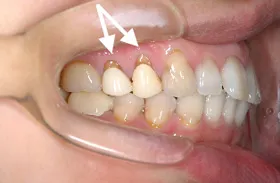

■治療前

矢印の部分の歯茎が下がって、歯の根っこが見えています。